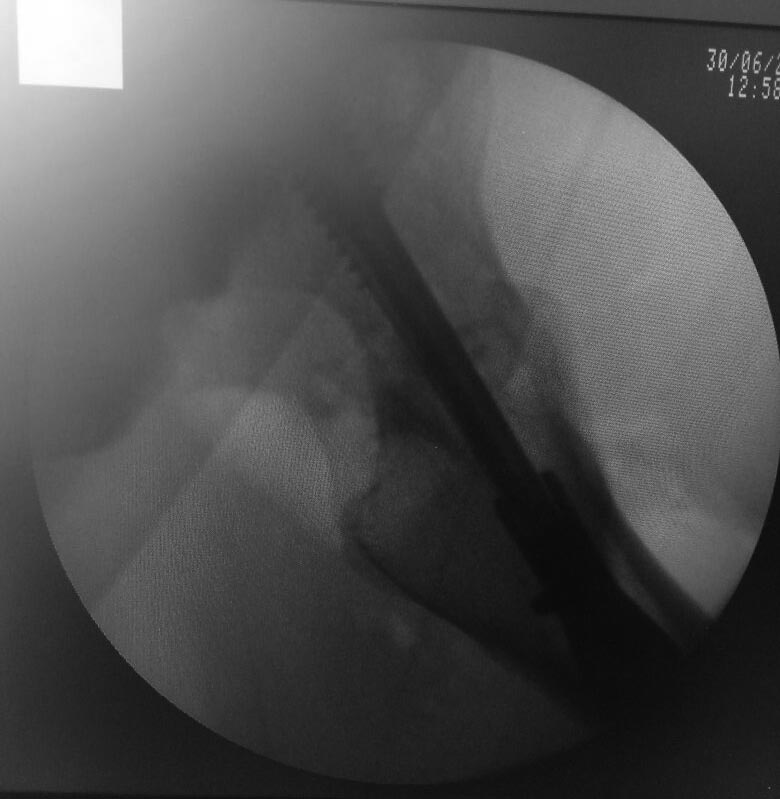

Rt 30 Июнь 2017, 12:58

Пока только фас. Бок технически не получилось (АВФ бедро-голень на уровне колена). Профиль С ЭОПа.